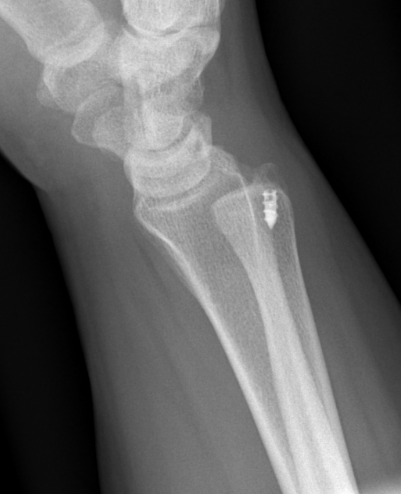

Xray

True lateral

- radial styloid overlies proximal scaphoid / lunate / triquetram

Dorsal subluxation of the distal ulna

CT